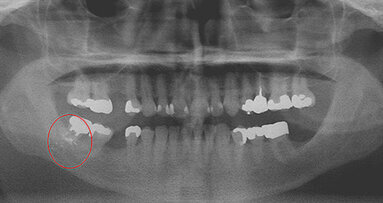

While numerous medical reports and studies describe foreign bodies embedded in the soft tissue of the oral cavity either by traumatic injury or caused ...